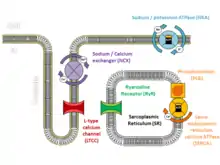

Excitation-contraction coupling

The arrhythmias that those with CPVT experience are caused by abnormalities in the way that cardiac muscle cells control their levels of calcium.[11] Calcium interacts with the protein fibres or myofibrils inside the cell that allow the cell to contract, and the concentration of calcium within each cell needs to be tightly regulated. During each heartbeat, the concentration of calcium must rise to allow the muscle to contract and then fall to allow the muscle to relax, a process achieved by using a store within the cell known as the sarcoplasmic reticulum.[12]

At the start of each heartbeat, calcium is released from the sarcoplasmic reticulum through specialised channels known as ryanodine receptors.[12] Ryanodine receptors open when the concentration of calcium near the channel increases. This happens when, in response to an electrical signal from the cell membrane called an action potential, a small amount of calcium flows across the cell membrane into the cell through L-type calcium channels, many of which are located on specialised inpouchings of the membrane called T-tubules designed to bring these surface ion channels close to the sarcoplasmic reticulum.[13]

The increase in calcium concentration triggers ryanodine receptors on the sarcoplasmic reticulum to release a puff of calcium known as a calcium spark. Each spark triggers the release of further sparks from neighbouring ryanodine receptors to create an organised rise of calcium throughout the cell known as a calcium transient. At the end of each heartbeat, calcium is pumped back by a protein called SERCA along with its regulatory protein phospholamban. The calcium is then held within the sarcoplasmic reticulum by a protein called calsequestrin.[12]

Fine-tuning of this process can be achieved by phosphorylating these proteins. As an example, during exercise catecholamines activate beta-adrenoceptors on the cell surface, which trigger protein kinase A to phosphorylate the L-type calcium channel, increasing the flow of calcium into the cell. Simultaneously, phosphorylation of the regulatory protein phospholamban causes more calcium to be drawn up into the sarcoplasmic reticulum. The overall effect of this is to generate a larger calcium transient with each beat, leading to a more forceful contraction.[13]

Calcium-dependent arrhythmias

Alterations to the proteins involved in excitation-contraction coupling can disrupt this carefully regulated process. In those with CPVT, the normally tight regulation of calcium can become deranged, leading to arrhythmias.[11] While calcium is generally released from the sarcoplasmic reticulum in response to an action potential, calcium sparks can also occur spontaneously. In a healthy heart, a spontaneous calcium spark is generally an isolated event and goes no further, but if ryanodine receptors or the proteins that regulate them are abnormal, these sparks can trigger releases from neighbouring ryanodine receptors which spread throughout the cell as a calcium wave.[11] These calcium waves are much more likely to occur when cardiac muscle cells are stimulated by catecholamines such as adrenaline, which increase the concentration of calcium within the sarcoplasmic reticulum and sensitise the ryanodine receptors.[14] The uncontrolled wave of calcium can be forced out through the cell membrane via the sodium-calcium exchanger, causing an electric current known as a delayed afterdepolarisation. Afterdepolarisations, if large enough, can trigger additional action potentials, premature ventricular contractions, or sustained arrhythmias.[15]